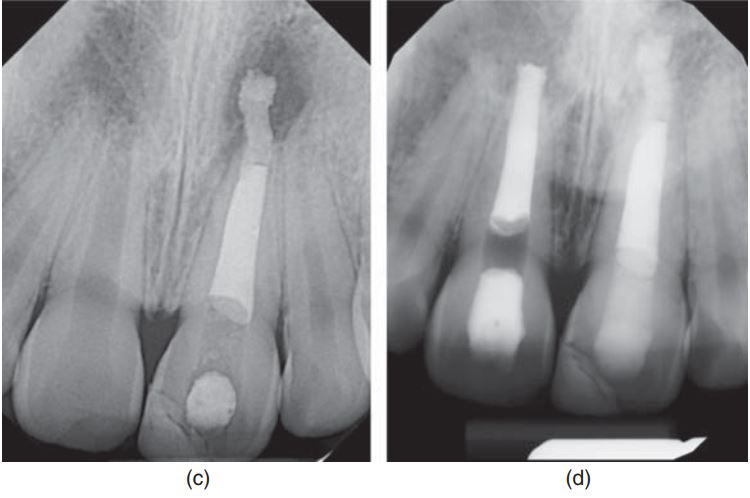

Hình 17.6. Lấy tủy buồng bằng MTA ở răng cửa giữa hàm trên chưa đóng chóp. (a) X quang 3 tháng sau khi điều trị. Chú ý hình ảnh cầu ngà. (b) X quang 6 tháng sau khi điều trị. Cầu ngà đã dày lên. (c) X quang 3,5 năm sau khi điều trị. Chân răng đã phát triển hoàn tất. Cầu ngà dày nhưng chân răng không thấy dấu hiệu canxi hóa bất thường.

Hình 17.7. Lấy tủy buồng bằng canxi hydroxit ở răng cửa giữa hàm trên chưa đóng chóp. (a) X quang trước điều trị. (b) X quang 12 tuần sau điều trị cho thấy cầu ngà.

(c) X quang 6 tháng sau. (d) X quang 2 năm sau. Chân răng đã phát triển hoàn tất. (e) X quang 3 năm sau. Ống tủy không bị canxi hóa.